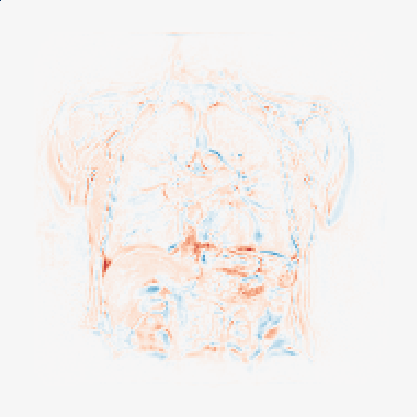

Finally, in Figure 2, we present the deformed image produced by the proposed method on coronal view for a single patient in the two different moments of the respiratory cyrcle. The grids were superimposed on the images, indicating the displacements calculated by the network. The last column shows the difference between the reference and deformed image. One can observe that the majority of the errors occur on the boundaries, as the network fails to capture large local displacements.